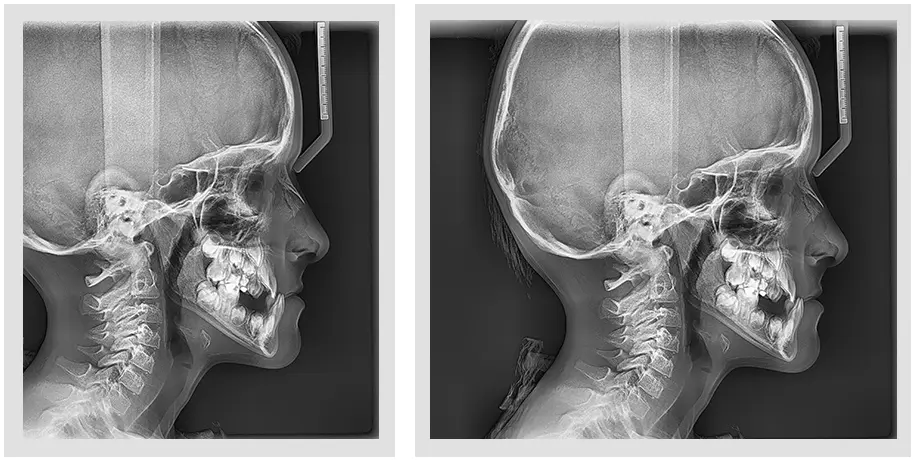

This facory certified Vatech PaX-i SC pan ceph X-ray machine provides consistently clear and detailed panoramic and cephalometric X-ray images, enhancing diagnostic precision and fostering greater treatment acceptance. With dedicated, built-in sensors for both panoramic and cephalometric imaging, this machine ensures exceptional digital imaging quality, while also boosting practice efficiency.

Optimal image for accurate diagnosis - Two Dedicated Sensors